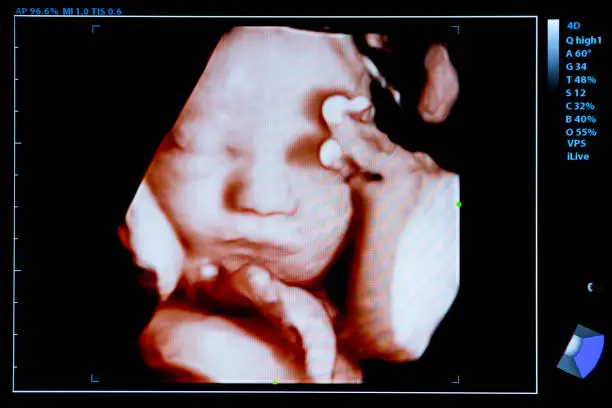

착상혈은 배란 후 수정된 난자가 자궁 내벽에 착상하는 과정에서 발생할 수 있는 출혈로, 이는 보통 배란 후 6일에서 12일 사이에 나타납니다. 수정란이 자궁벽에 자리 잡는 과정에서 자궁 내막의 일부가 손상되면서 소량의 출혈이 발생하게 되는 것입니다. 이 출혈은 보통 연한 분홍색이나 갈색을 띠고, 매우 가벼운 양으로 나타나며 길게는 며칠 정도 지속될 수 있습니다. 하지만 모든 여성들이 착상혈을 경험하는 것은 아니며, 개인에 따라 착상혈의 양상은 매우 다양하게 나타날 수 있습니다.

착상혈이 발생한 후 임신 여부를 정확하게 확인하려면 임테기를 적절한 시기에 사용하는 것이 중요합니다. 착상 후 hCG 호르몬이 분비되기 시작하지만, 임테기에서 이를 감지할 수 있을 정도로 hCG 수치가 높아지기까지는 시간이 걸립니다. 일반적으로 배란 후 14일 정도가 지나야 임신 테스트기를 통해 임신 여부를 정확하게 확인할 수 있습니다. 따라서 착상혈이 있었다고 해서 바로 임테기를 사용하는 것보다는, 며칠 후 테스트를 시도하는 것이 보다 정확한 결과를 얻는 데 도움이 됩니다.

임테기에서 한 줄이 나왔을 때는 실망할 필요 없이 일정 기간 후 다시 테스트를 시도해 보는 것이 좋습니다. 만약 착상혈 이후에도 한 줄이 계속 나오거나 생리와 유사한 출혈이 지속된다면, 의사와 상담하여 보다 정확한 진단을 받는 것이 안전합니다. 임신 테스트기는 착상 후 일정 시간이 지나야 정확한 결과를 제공하기 때문에, 성급한 결론을 내리기보다는 신중하게 접근하는 것이 중요합니다.